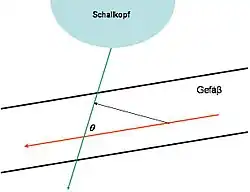

Prinzip

Der Doppler-Effekt tritt immer dann auf, wenn Sender und Empfänger einer Welle sich relativ zueinander bewegen. Zur Bestimmung der Blutflussgeschwindigkeit in den Blutgefäßen oder im Herzen detektiert man das von den Blutkörperchen (Erythrozyten) reflektierte Echo. Das reflektierte Signal ist um eine bestimmte Frequenz im Vergleich zur vom Schallkopf ausgesandten Frequenz verschoben: die Doppler-Frequenz. Von dem „ruhenden“ Sender, dem Schallkopf, geht eine Welle der Frequenz aus; ein sich bewegendes Teilchen mit der Flussgeschwindigkeit reflektiert den Schall mit der Frequenzverschiebung . Die gesamte Frequenzverschiebung (mit Winkel zwischen Teilchenbahn und Schallstrahl, : Schallgeschwindigkeit) beträgt

- .

Aus ihrem Vorzeichen lässt sich die Flussrichtung rekonstruieren. Bei gegebener Geschwindigkeit ist die Frequenzverschiebung umso größer, je größer die Sendefrequenz ist. Im Bereich von 2 bis 8 MHz und Flussgeschwindigkeiten von wenigen mm/s bis zu 2 m/s ist etwa 50 Hz bis 15 kHz. Zur exakten Geschwindigkeitsmessung ist die Bestimmung des Winkels (Doppler-Winkel) zwischen Schallausbreitungsrichtung und Bewegungsrichtung des Erythrozyten (Richtung des Blutgefäßverlaufes) notwendig. Da das Doppler-Prinzip winkelabhängig ist und die Kosinus-Funktion in die Geschwindigkeitsberechnung eingeht, kommt es infolge des sich mit zunehmendem Winkel ändernden Anstiegs der Kosinus-Funktion zu unterschiedlich starken Einflüssen gleicher Winkelmessfehler auf die errechnete Geschwindigkeit. Da sich Bewegungen des Schallkopfes in der Realität kaum vermeiden lassen, nehmen die Fehler, die durch diese Variation des Winkels entstehen, überproportional zu, wenn der Winkel zwischen Schallausbreitung und Gefäßrichtung untersuchungsbedingt variiert. Daher wird allgemein empfohlen, Aussagen zu Geschwindigkeiten bei Untersuchungen mit einem Doppler-Winkel > 60° zu unterlassen. Die Abhängigkeit vom Winkel lässt sich aber eliminieren, beispielsweise durch Verwendung von Stereomessköpfen.